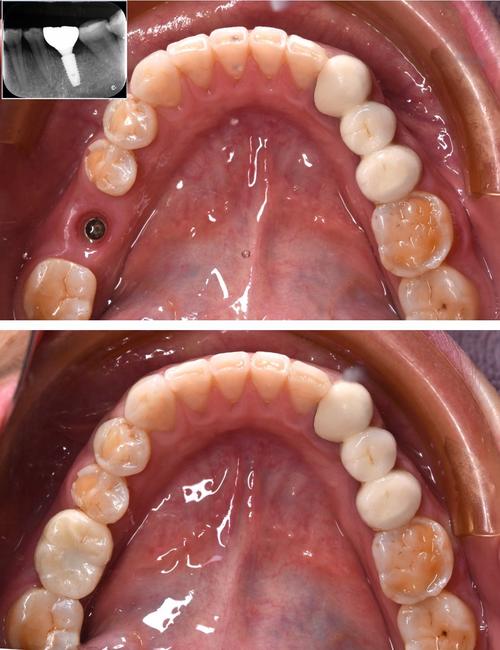

(图片来源网络,侵删) -

基台与球帽附着体安装:

- 骨结合完成后,切开牙龈暴露种植体,安装愈合基台2周,使牙龈形成袖口形态。

- 拆除愈合基台,选择合适角度的基台(补偿种植体植入角度偏差),在基台上安装球状突起(阳极)。